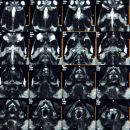

TURTLE MRI SCAN